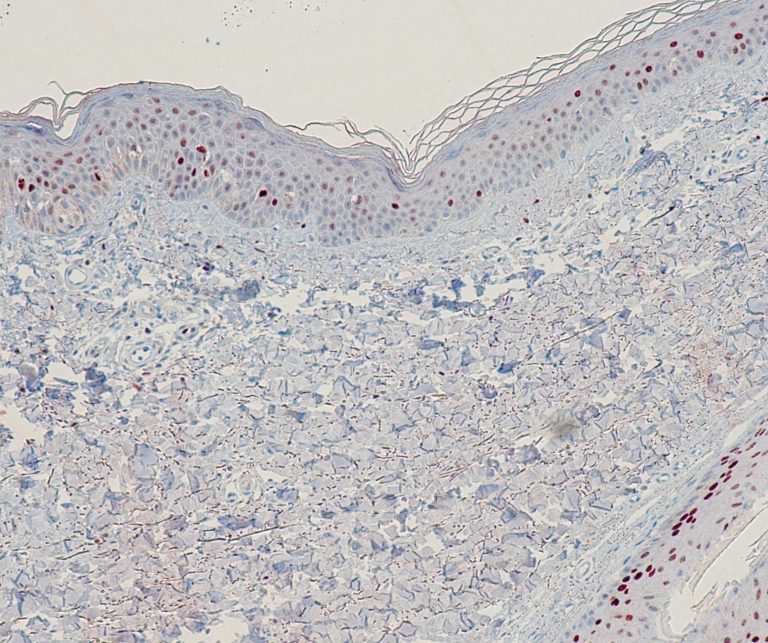

Vascular Pathology

Gastrointestinal (GI) Pathology

General Marker

Breast Pathology

Endocrine Pathology

Gynecological Pathology

Neuropathology

Infection Markers

Lung Pathology

Urinary Tract Pathology

Transplantation Pathology

Soft Tissue Pathology

Hematopathology